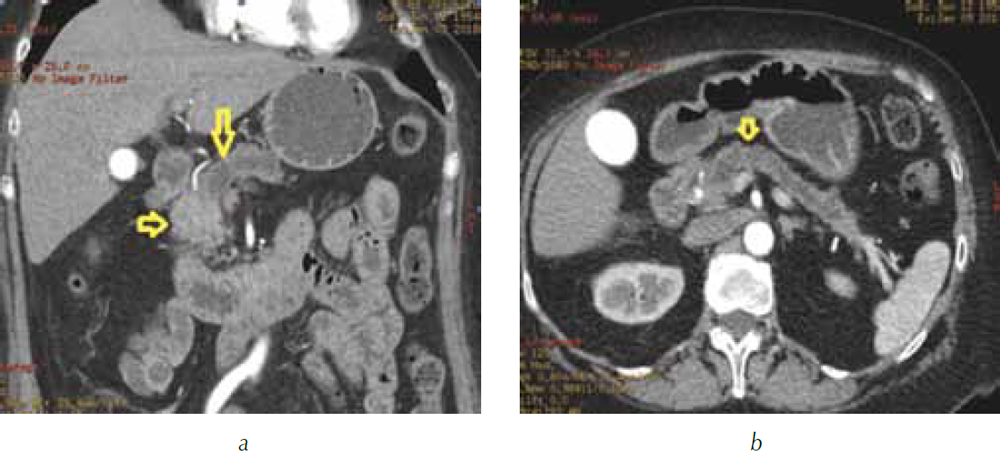

В панкреатическую фазу опухоль по степени накопления контрастного вещества не отличалась от окружающей паренхимы поджелудочной железы и также была не видна (рис. 3).

Рис. 3. Компьютерная томография гепатопанкреатодуоденальной зоны в артериальную фазу сканирования: а — трехмерная реформация в коронарной проекции в алгоритме MIP. Головка поджелудочной железы однородной структуры, равномерно накапливает контрастный препарат (короткая стрелка), опухоль не видна. В теле поджелудочной железы расширен главный панкреатический проток (длинная стрелка); b — трехмерная реформация в аксиальной проекции в алгоритме MIP. В теле и хвосте поджелудочной железы расширен главный панкреатический проток (стрелка)

При анализе перфузионных карт был выявлен контакт опухоли на уровне конфлюэнса с правой боковой стенкой воротной вены с уплощением ее контура без признаков инвазии (рис. 6), от магистральных артерий опухоль была отделена прослойками жировой ткани.

Рис. 6. Компьютерная томография гепатопанкреатодуоденальной зоны в портальную фазу сканирования: а — трехмерная реформация в алгоритме MIP. Перешеек поджелудочной железы (стрелка) прилежит к портомезентериальному стволу, границы опухоли не видны; b — перфузионная карта скорости кровотока (BF). Опухоль (стрелка) в головке поджелудочной железы вплотную прилежит к правой боковой стенке воротной вены (стрелка) без сохранения жировой прослойки. Контур вены в месте контакта с опухолью уплощен